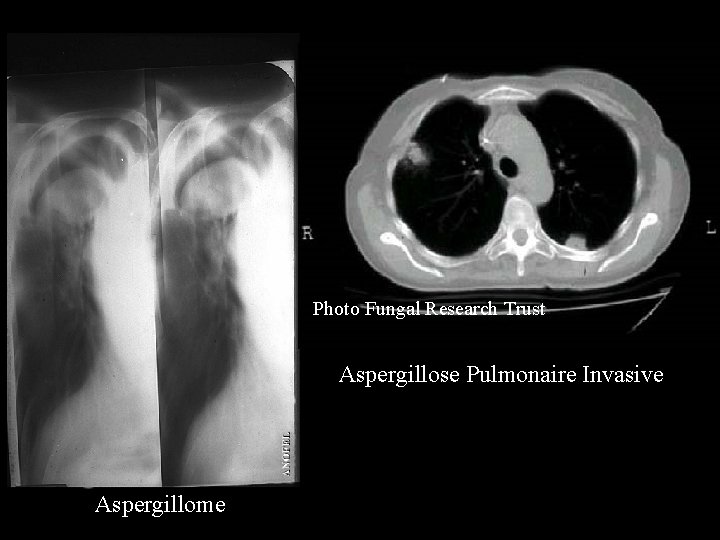

ASPERGILLOSES - FORMES CLINIQUES - ASPERGILLOME BRONCHIQUE ASPERGILLOSE PULMONAIRE INVASIVE ASPERGILLOSES IMMUNO-ALLERGIQUES ASPERGILLOSE DES SINUS ASPERGILLOSE DU CONDUIT AUDITIF EXT. KERATITE ASPERGILLAIRE ETC. . .

Photo Fungal Research Trust Aspergillose Pulmonaire Invasive Aspergillome

DIAGNOSTIC - CLINIQUE + IMAGERIE - EXAMEN DIRECT DES ECHANTILLONS : * MISE EN EVIDENCE DE FILAMENTS - CULTURE : * SUR MILIEU DE SABOURAUD * PERMET LE DIAGNOSTIC SPECIFIQUE